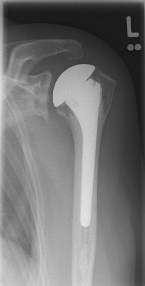

Abbildung7Abbildung8

Short stem prostheses as modern implants for omarthrosis and acetabular wear

left: X-ray image of a short-shaft prosthesis

right: Short-shaft prosthesis (Affinis Short type, Mathys company)